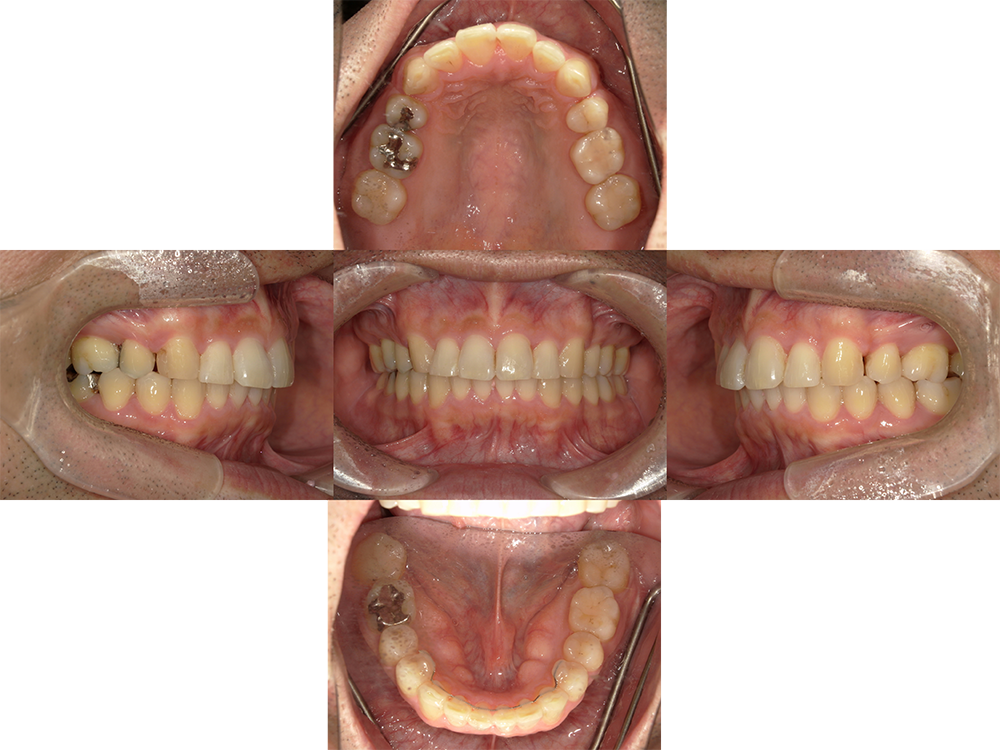

Before

After

主訴

叢生

装置

ワイヤー矯正

治療期間

2年2ヵ月(現在保定中)

性別

男性

年齢

40歳

抜歯箇所

上顎左右4番

費用

367,400円

非抜歯にてマウスピース矯正(インビザライン)を他医院から転勤にて転医。 インビザラインのアカウントを引継ぎ非抜歯にて治療を継続。

仕事の都合上、マウスピースを装着する時間が短いので治療が進まないとのことで、上顎左右4番の抜歯によるワイヤー矯正に変更することに。